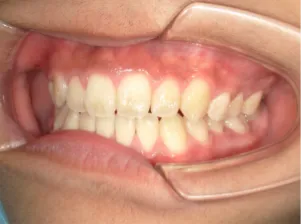

治療中④中2:マルチブラケット法へ移行:上下正中を合わせたい

*マルチブラケット法

治療後⑤中3:咬合治療終了 マルチブラケット法の期間は9か月